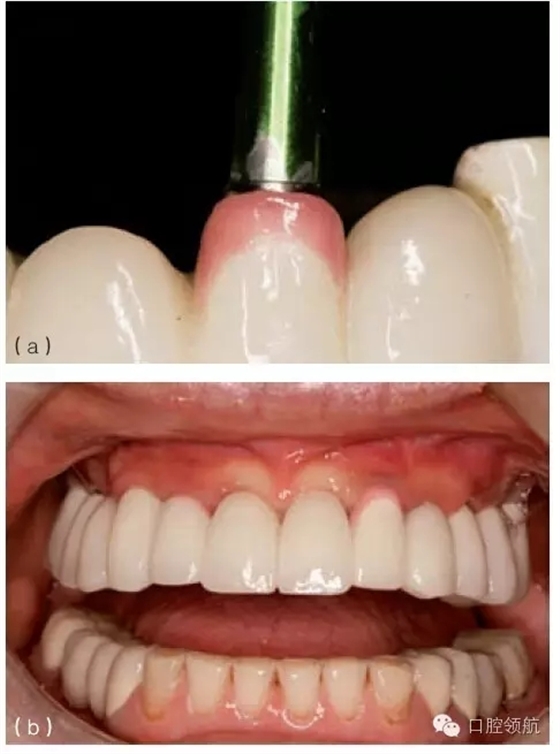

在種植體植入之前,有必要確定最終的修復(fù)方案,并且計(jì)算放置種植體修復(fù)部件所需要的空間。例如,對(duì)于單個(gè)粘結(jié)固位的種植修復(fù)體,從種植體平臺(tái)到對(duì)頜牙,最少需要7mm的空間。這個(gè)空間包括以下組成部分:基臺(tái)距對(duì)頜牙牙合面2mm;對(duì)粘結(jié)固位來說,即便聚合度非常平行的情況下,也至少需要4.5mm的預(yù)備高度,才能滿足固位要求;基臺(tái)與種植體交接的拋光肩領(lǐng)需要0.5mm。如果牙合間距離較?。ㄈ?.5~5mm),可以制作螺絲固位修復(fù)體(或UCLA的一體化冠)(圖9.23a,b)。實(shí)施種植手術(shù)時(shí),必須考慮牙齦厚度及牙槽骨的水平。若有需要,可以施行牙槽嵴切除術(shù),以獲得額外的牙合間距離。另外,種植體可以高于、低于或平齊牙槽嵴頂,以便與未來的修復(fù)體匹配。但當(dāng)在修復(fù)期間考慮這些問題時(shí),剩下的選擇就非常有限,只能在粘結(jié)固位或螺絲固位中選擇一種。有時(shí),可以選磨對(duì)頜牙,來獲取少量的修復(fù)空間。另外,如果需要恢復(fù)垂直高度的話,可以通過升高咬合來獲得牙合間距離。

圖9.23 (a) 頰面觀, 牙合間距離不足(5mm)(相對(duì)于粘結(jié)固位),需要制作螺絲固位式修復(fù)體。(b)牙合 面和舌側(cè)觀,完成的螺絲固位式修復(fù)體。